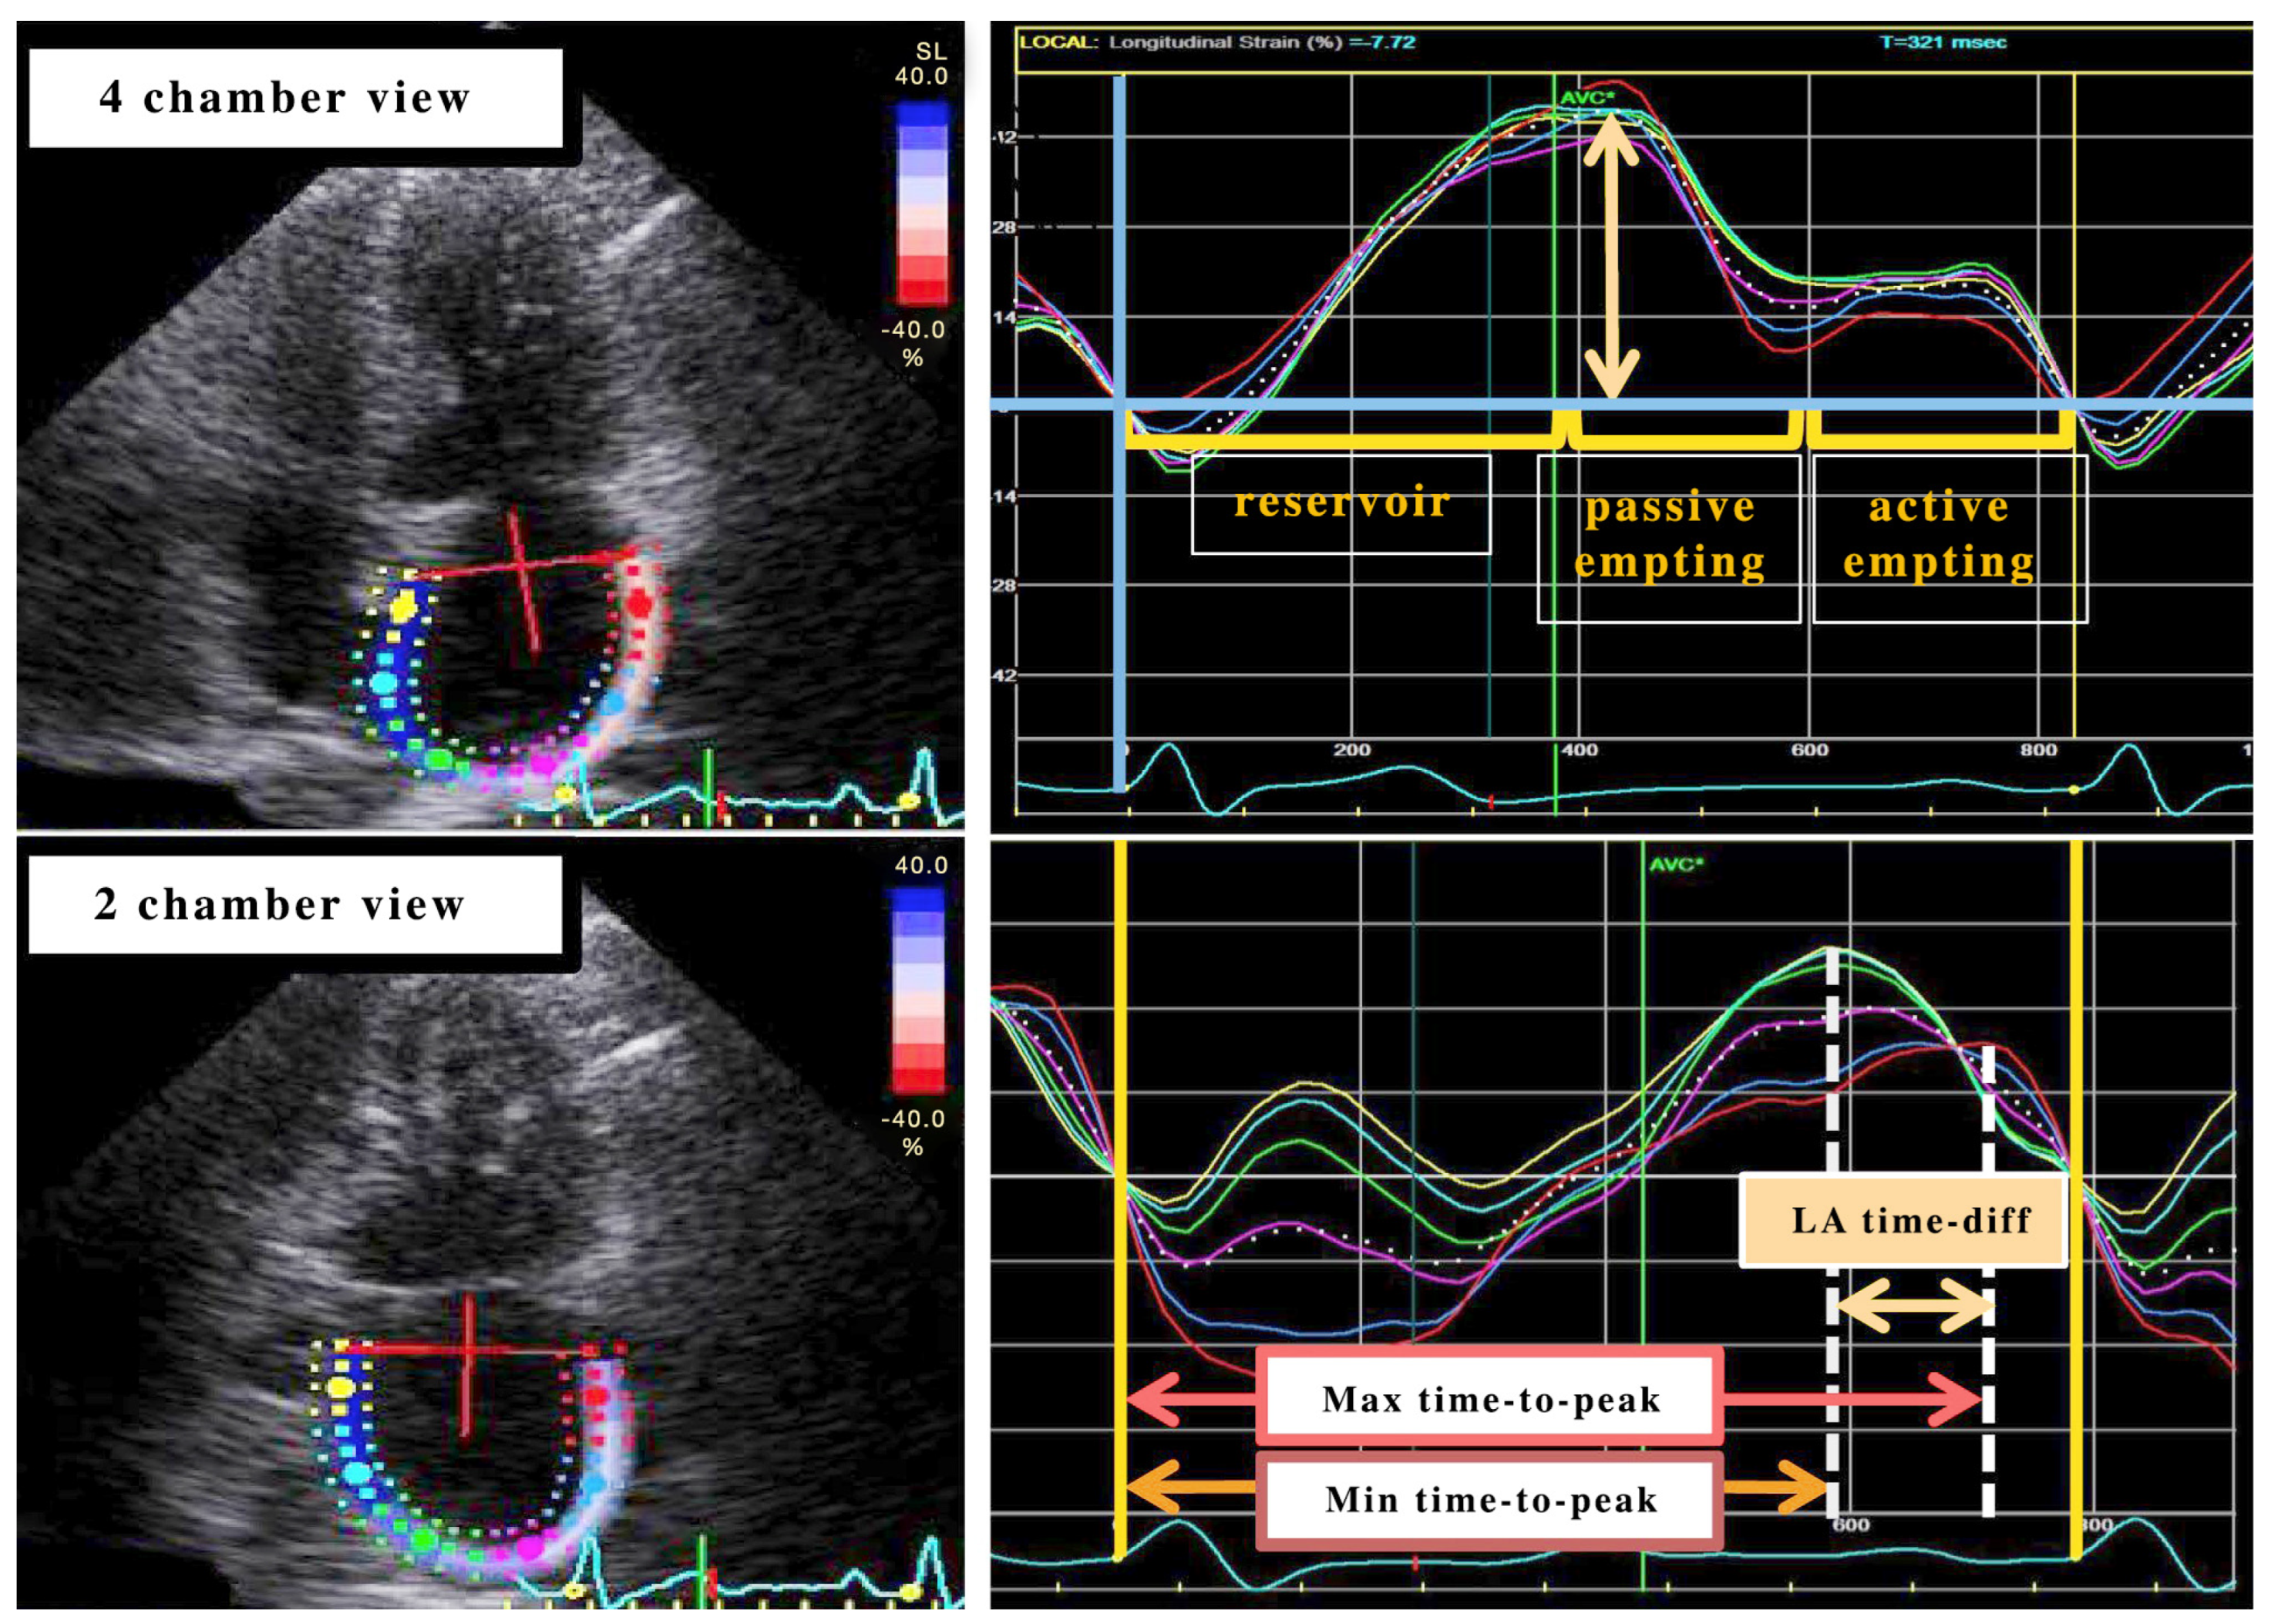

3.2. Measuring Left Atrial (LA) Strain